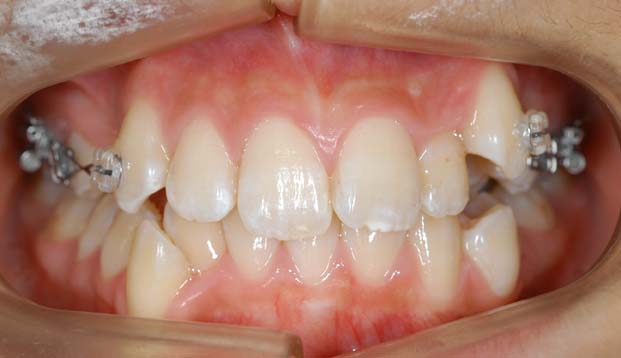

1.叢生(乱ぐい歯) 歯が重なり合ってでこぼこしています

治療後